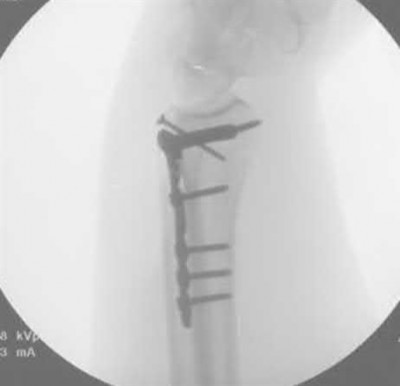

A 64-year-old woman is thrown off a horse, sustaining the injury shown in Figures A and B. She undergoes surgical fixation as seen in Figures C through E. What is the most commonly reported complication of this procedure?

The patient in the scenario has a 2-part proximal humerus fracture treated with a locking plate as seen in Figures A-E. The most common complication with the use of this implant is screw penetration. The terms screw cut out and penetration are often used interchangeably in the literature with cut out appearing more frequently in reports regarding intertrochanteric fractures.

Owsley et al retrospectively reviewed 53 proximal humerus fractures treated with locking plates and the same post-operative protocol. The most common complication was screw cut out or penetration, followed by varus displacement. They concluded that 3 and 4-part fractures in patients over 60 years have a higher incidence of failure.